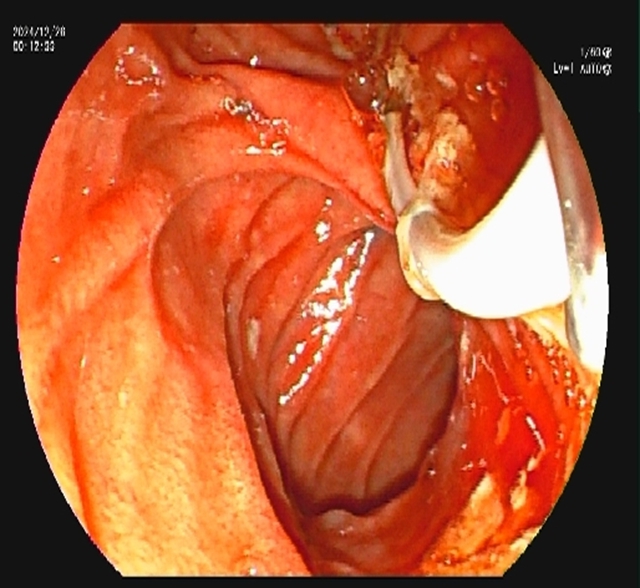

内镜到达十二指肠乳头时,切开乳头的瞬间,大量白色脓液喷涌而出(证实胆道高压、感染极重);随后用球囊扩张乳头(扩大开口),顺利取出嵌顿的结石。

术后,放置鼻胆管持续引流脓性胆汁(当天引出300ml浑浊胆汁)。